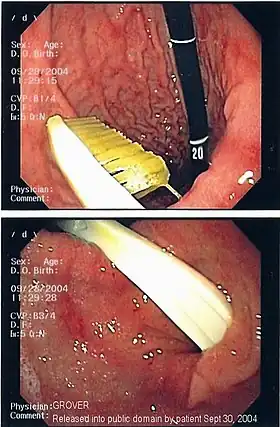

A coin seen on AP CXR in the esophagus

A coin seen on lateral CXR in the esophagus